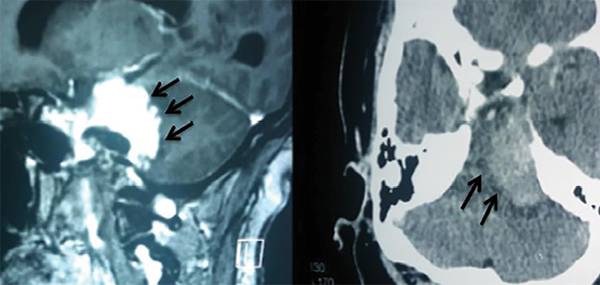

Por definición, los meningiomas petroclivales tienen su origen medial a los pares craneales V, VII, VIII, IX, X y XI, y pueden alcanzar el tentorio.1,3,5,6 A menudo se extienden hacia la fosa media, el seno cavernoso y la cisterna prepontina (Figura 1). Pueden descender al agujero magno, pudiendo invadir la piamadre y causar compresión del tronco encefálico. En los casos en que hay edema del tronco encefálico (hipodensidad en la tomografía o hiperseñal enT2 en la resonancia magnética) o una forma dentada e irregular del tumor sobre el tejido cerebral, la extracción total es muy difícil o imposible sin causar déficits neurológicos3-5(Figura 2). Los meningiomas del clivus inferior (foramen magno), petrosos, tentoriales y del ala esfenoidal pueden alcanzar estas áreas, pero no se consideran de origen petroclival.6

Figura 2: Resonancia magnética que muestra la forma dentada del borde del tumor (izquierda) y tomografía que muestra edema del tronco encefálico. Éstos son hallazgos que indican la ausencia de un buen plan de disección entre el tumor y el tronco encefálico.